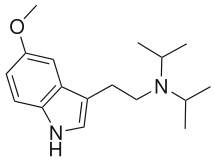

Substituted tryptamines, or serotonin analogues, are organic compounds which may be thought of as being derived from tryptamine itself. The molecular structures of all tryptamines contain an indole ring, joined to an amino (NH2) group via an ethyl (−CH2–CH2−) sidechain. In substituted tryptamines, the indole ring, sidechain, and/or amino group are modified by substituting another group for one of the hydrogen (H) atoms.

| DiPT | artificial | H | CH(CH3)2 | CH(CH3)2 | N,N-diisopropyltryptamine | 14780-24-6 |